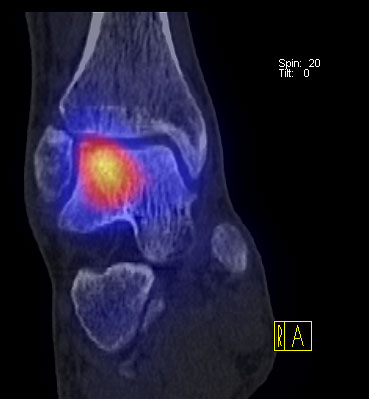

Die Kombination von SPECT und CT in einem Untersuchungsgang bringt wie bereits oben erwähnt eine erhöhte Ortsauflösung und artefaktfreie Darstellung von Knochenstoffwechselveränderungen der SPECT bei gleichzeitig excellent guter anatomischer Darstellung/Zuordnung durch die CT 3. Auf die Vorteile der CT gegenüber dem konventionellen Röntgen muss nicht mehr besonders eingegangen werden. Besonders eignet sich die „SPECT-CT“ zur Diagnostik von Fußerkrankungen (Biersack HJ et al. 2012).

Aufgrund der optimalen funktionellen Darstellung (PET) und der entsprechend guten anatomischen Bildgebung kann dieses kombinierte Untersuchungsverfahren viele Fragestellungen auch im Bereich des Fußes beantworten. Exemplarisch werden folgende Indikationen erwähnt. Abklärung von Infektionen im muskuloskelettalen Bereich 45, Untersuchungen von unklaren Fußschmerzen (Biersack HJ et al. 2012), präoperative Bildgebung beim Charcot-Fuß/diabetischer Fuß 31.